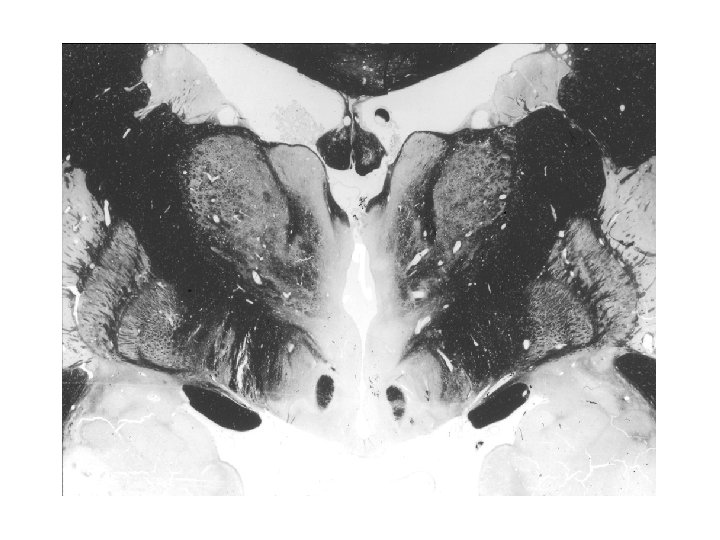

Gömöri’s staining

Hypothalamo-hypophysis rendszer Két részből, a nagysejtes hypothalamo-neurohypophysealis és a kissejtes tubero-infundibuláris rendszerből tevődik össze. A nagysejtes supraopticus és paraventriculáris neuronok vasopressint és oxytocint termelnek, axonjaik jelentős része (a supraopticus esetében az összes) a neurohypophysisben végződnek, ami quasi raktára a vasopressinnek és az oxytocinnak. A tubero -infundibuláris neuronok a hypophysis elülső részében levő endokrin sejtek neurohormonjaik termelésének szabályozását és felszabadításukat (release -t) végzik. A hypothalamus különböző részeiben termelődő neurohormonok nem közvetlen úton, hanem neurohumorális transzport révén jutnak a hypophysisbe: axonjaik az eminentia mediana vér-agy gát-mentes kapillárisaiba ürítik szállított termékeiket, melyek a portális erek révén jutnak a hypophysis elülső lebenyébe.